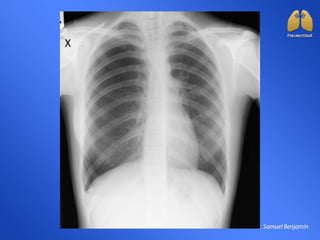

Figura 5. Hipertransparência à esquerda. Atelectasia de pulmão

esquerdo.

Figura 5. Hipertransparênciaà esquerda. Atelectasia de pulmão esquerdo.